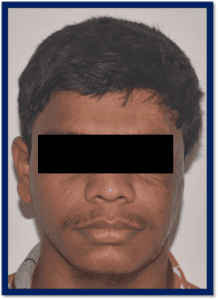

The Department of Prosthodontics and Crown & Bridge, in association with various Departments of Goa Medical College (Neurosurgery, Plastic Surgery, Surgery, Ophthalmology, and ENT), carries out complex rehabilitations of patients suffering from various developmental and acquired defects.

- Prostheses for maxillofacial defects